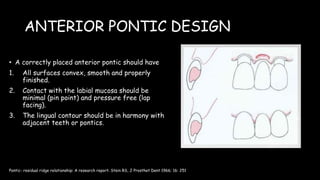

The document discusses pontic design for fixed dental prostheses. It covers pretreatment assessment of residual ridge contours, classifications of ridge deformities, surgical modification techniques, and ideal requirements for pontics. Pontic designs are classified based on their shape and materials. Factors in pontic selection include esthetics and oral hygiene. Common designs for anterior and posterior regions are described, including sanitary, ovate, and saddle pontics. Biological considerations for pontic design involve maintaining the residual ridge, abutment teeth, and supporting tissues.